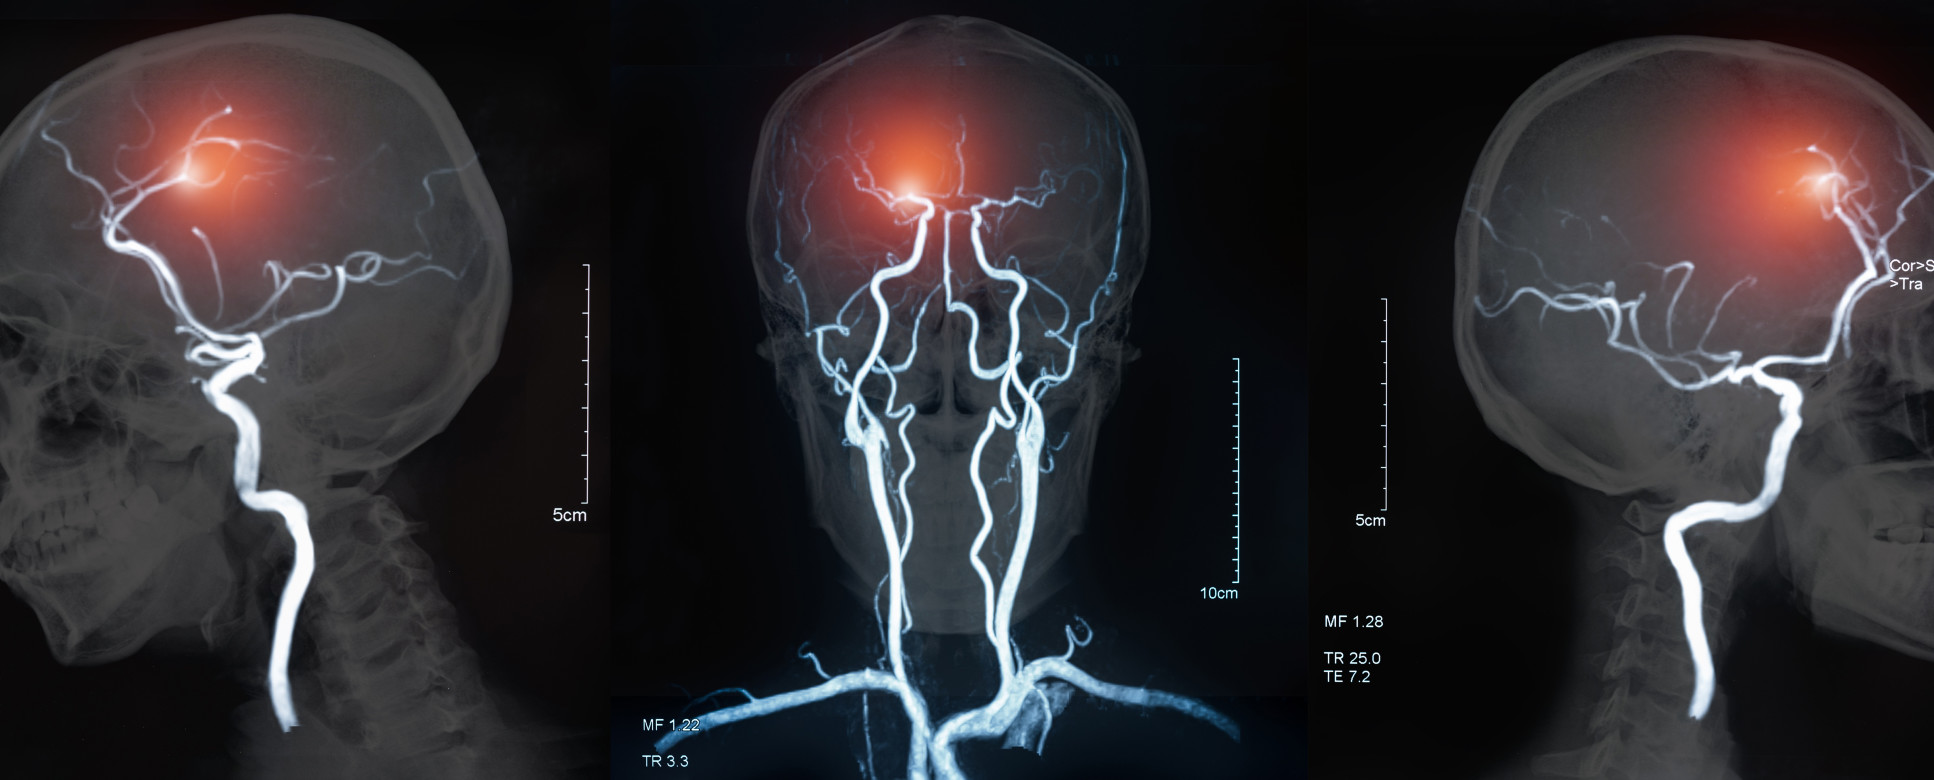

MRI of the blood vessels in the brain and cerebrovascular disease or or hemorrhagic stroke. brain stroke x-ray image.

Stroke affects more than more than 100,000 people per year in the UK, and occurs when the supply of blood to the brain is reduced or blocked. It most commonly arises in the cerebral artery, which directly affects the motor cortex, and can cause substantial impairments in the motor abilities of patients affecting walking and speech.

Stroke and Parkinson’s are only two examples of the impairments targeted by the new NISNEM technology. The researchers hope the new technology will detect brain abnormalities to help early diagnosis of these progressive diseases as well as developing non-invasive treatments.

The researchers hope the new technology will detect brain abnormalities to help early diagnosis of progressive diseases like stroke